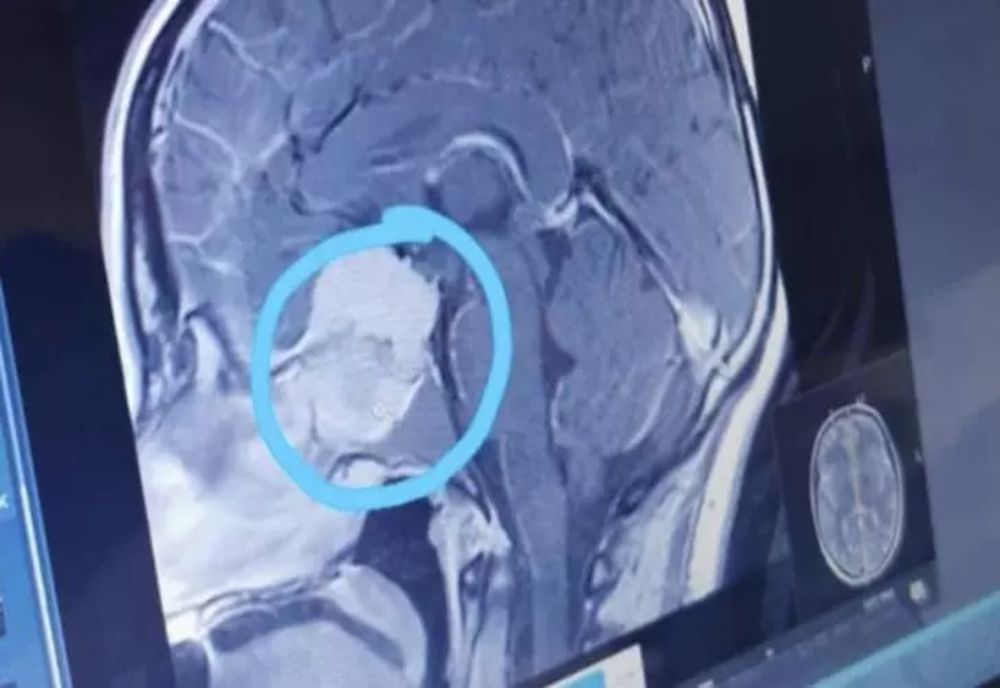

Oamenii de știință de la Școala de Medicină de la Universitatea din Maryland au efectuat un studiu pentru a afla care sunt grupele sanguine cu un risc mult mai mare de a suferi un accident vascular cerebral la o vârstă fragedă.

Astfel, s-a constatat că cei mai nenorocoși sunt purtătorii grupei sanguine A, adică a doua grupă.

„Studiul a arătat că 48% dintre persoanele cu accident vascular cerebral timpuriu aveau grupa sanguină A. Încă a fost stabilit exact care este legătura, sunt necesare cercetări suplimentare care să confirme sau să infirme ipoteza noastră”, spun cercetătorii

La polul opus, persoanele cu grupa sanguină 0 (adică prima) sunt cel mai puțin susceptibile la această afecțiune periculoasă. Sau poate că îi afectează într-o etapă mai târzie a vieții, dar consecințele nu vor fi atât de fatale.